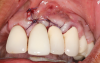

Following infiltration of the facial attached gingiva and palatal area with articaine hydrochloride 4% and epinephrine 1:100,000 (Septocaine®, Septodont [alternatively: Articadent®, Dentsply Sirona; Orabloc®, Pierrel]), an envelope releasing incision was made extending one full tooth over. To prevent trauma to the mucosal tissue, vertical incisions were not made (Figure 3). Incising the mucosa results in the release of prostaglandins and histamine, which increases postoperative discomfort. For this patient, staying in attached gingiva provided excellent control of the flap and allowed clear access to the apical lesion.

(3.) An envelope reflection was made with no vertical incisions, exposing the entire bony defect affecting the apical portion of the stable implant.

Figure 3